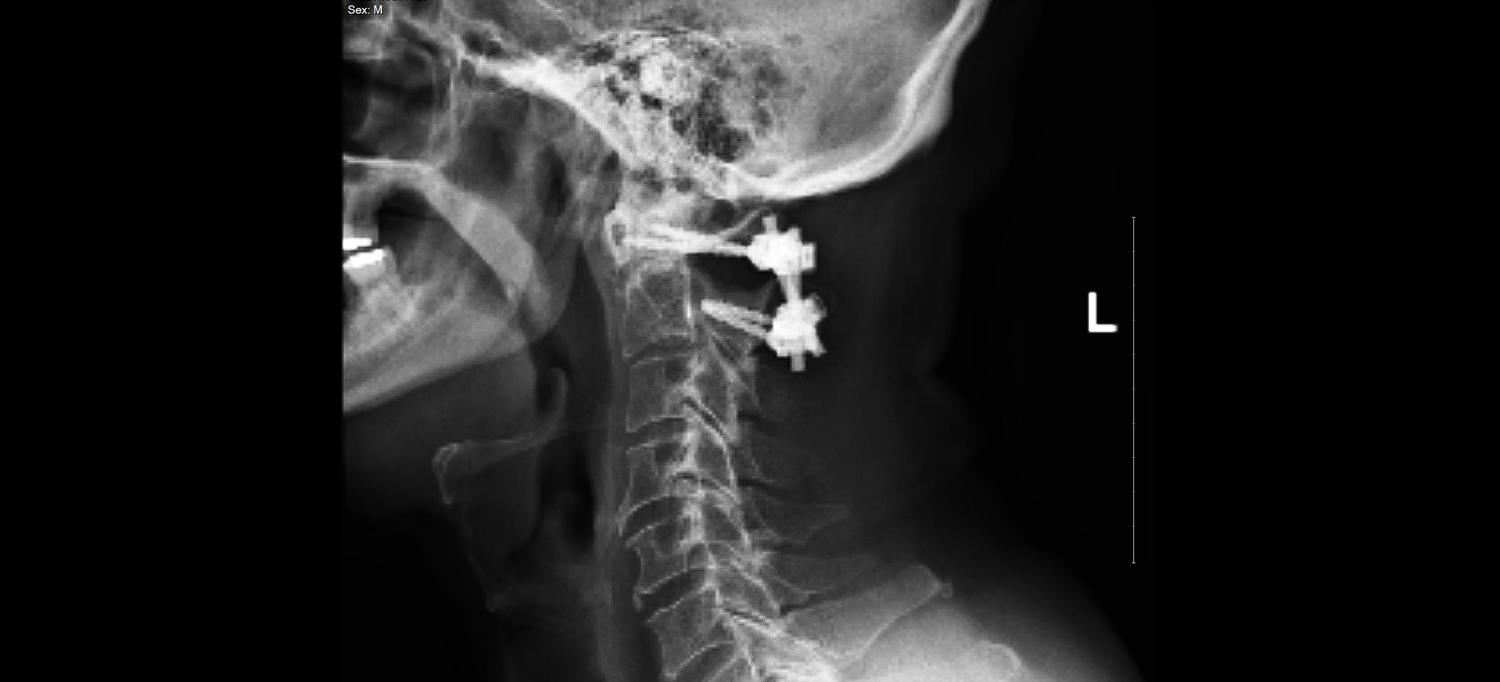

Instead, Dr. Jegede proposed a nonfusion approach called fracture fixation. Realigning Gibson’s first and second cervical vertebrae, he would fasten them with screws and rods, then remove the hardware when the fracture had healed, one year later.

Dr. Jegede performed the three-hour surgery on January 6, 2023, at NYU Langone’s Kimmel Pavilion. The surgery stabilized Gibson’s first and second cervical vertebrae with screws and rods until they healed, enabling Gibson to regain full range of motion in his neck.